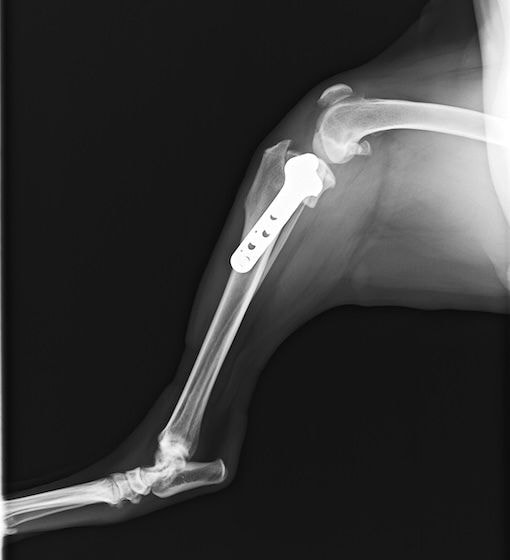

術後左後肢側面像

術前のTPAは左後肢33.1°右後肢26.8°でしたがTPLO実施により左後肢5.5°右後肢12°に矯正されました。